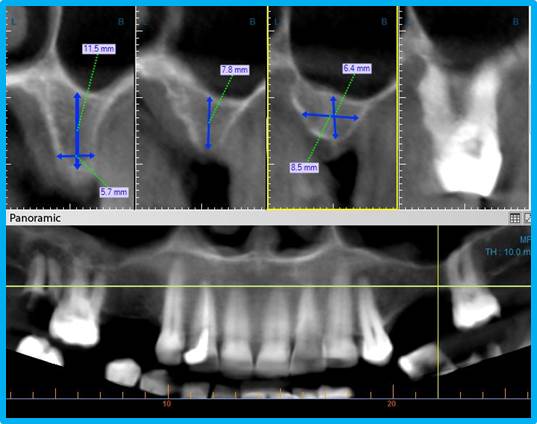

В медицинский план подготовки к процедуре входит выявление проблем, касающихся здоровья. Для этого имплантолог соберет анамнез и выяснит факторы риска. Затем потребуется пройти обследование. Врач попросит сдать анализы и выполнить компьютерную томограмму, рентгенологическое обследование или аналогичную процедуру, вроде https://x-rdv.ru/dlya-implantologov/, чтобы уточнить объем предполагаемого вмешательства.

Будьте готовы по просьбе врача после вмешательства пройти дополнительное обследование, наподобие https://x-rdv.ru/dlya-stomatologov-ortopedov/, чтобы проконтролировать корректность положения имплантов и состояние костной ткани.